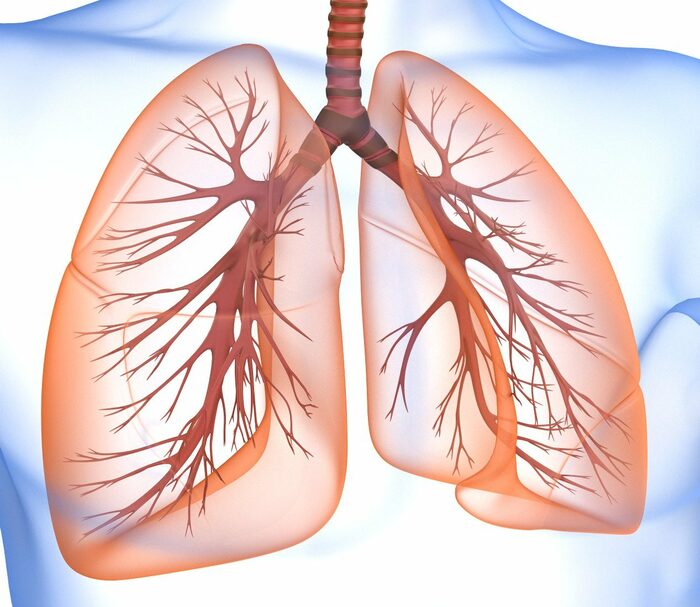

Здоровье дыхательной системы: бронхи и легкие

Раздел: Светлые идеи